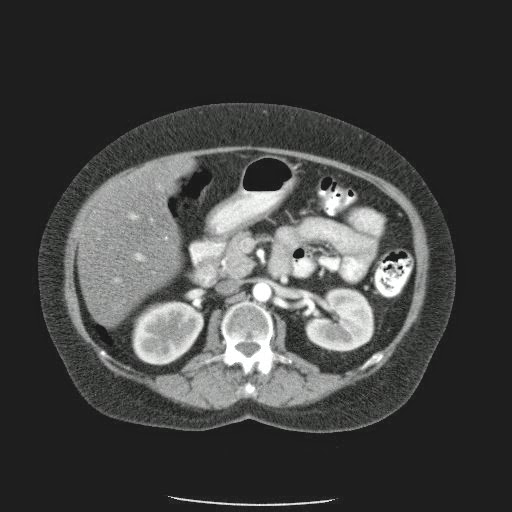

- ¿Hallazgos Escanografia?

2. Hay una colección de la pared abdominal en el flanco derecho, que realza en la periferia con el contraste, e intraabdominal tiene aire pero no me parece colección intraabdominal porque la grasa no está alterada.